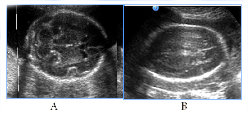

In the 3cases of mild and moderate fetal ventriculomegaly the adverse GPO was observed in 1 case, adverse CPO- in the other two,so any expression of the fetal hydrocephalic syndrome requires postnatal catamnesis observation (Figure 2).

Figure 2Mild and moderate fetal ventriculomegaly, 3cases.

Mild and moderate fetal ventriculomegaly, 3cases. A). Mild (border) fetal ventriculomegaly, the lateral ventricles thresholds expanding up to 11mm, without any clinical manifestations in neonatal stage, long-term neurological disorders by the end of the 2nd year age. B). Lateral ventricles are 15mm width in fetus with associated moderate hydrocephalus, infant death.